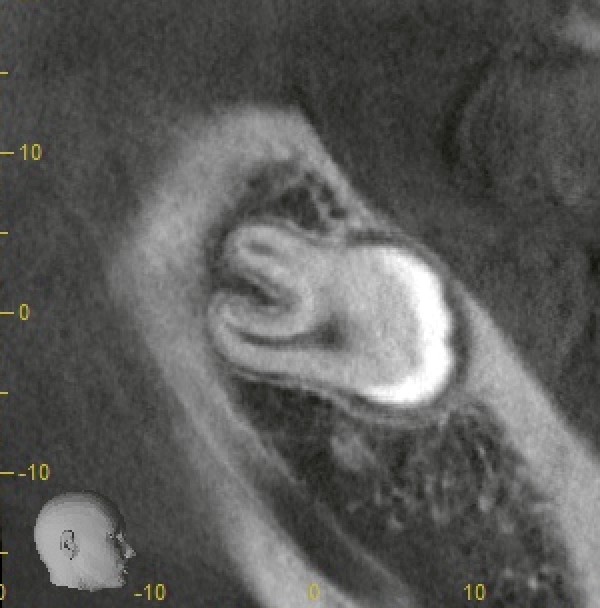

CT画像

こちらは神経との位置関係を確認したCT画像の一部です。

歯根は2根存在していますが、実際には神経との距離はある程度保たれていることが確認できます。

2D画像では神経に近く見えても、3Dで確認すると意外と距離があるケースは少なくありません。